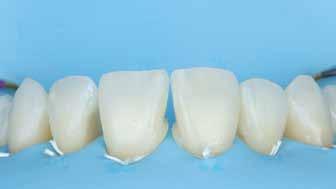

A cikkünkben bemutatásra kerülő eset ellátása során preparációt héjak készre vitele során a platinafólia technikát alkalmaztuk.

kívül vékonyak, és ezáltal a végleges rögzítésük előtt jelentős olyan minimál invazív kezelési eljárásnak számítanak, amely

elérni. A fent leírtak alapján bátran

preparációt nem igénylő héjak készítése mellett döntöttünk. A alkalmaztuk. Annak ellenére, hogy az elkészítésre kerülő héjak rendjelentős törésveszéllyel állunk szemben, összességében mégis amely segítségével kifogástalan esztétikai eredményeket lehet javasoljuk e módszer alkalmazását.